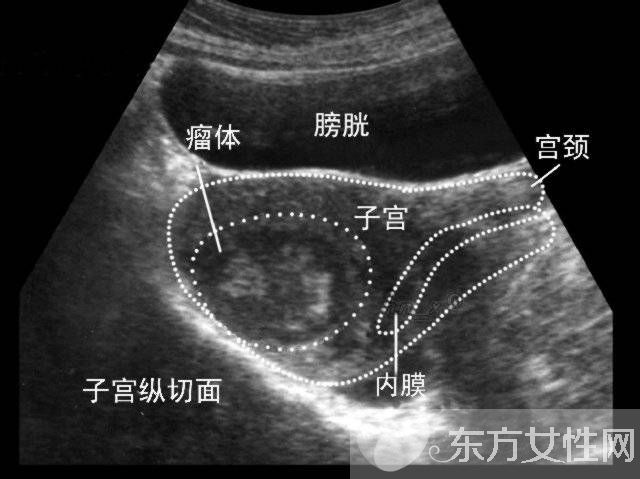

子宫肌瘤是女性子宫内多见的非恶性肿瘤,根据其在宫体内肌肉分布位置的不同,可分为肌壁间肌瘤、浆膜下肌瘤和黏膜下肌瘤,不过,肌瘤也可以同时在多种位置生长。